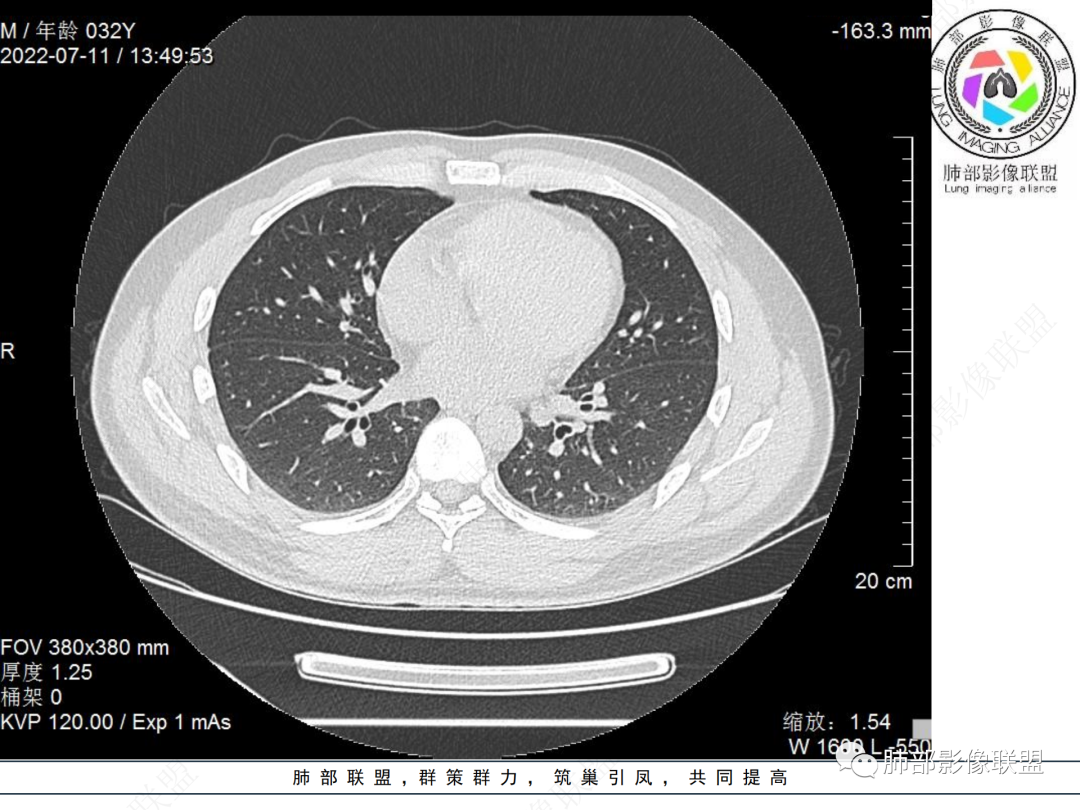

左肺下叶后基底段开口处结节,边缘光滑清楚,没有增强扫描,年轻男性患者痰血三天,考虑1.良性病变:腺瘤、错构瘤、平滑肌瘤

左肺下叶外后基底段气管内见结节状影,边缘部分清晰。考虑错构瘤,待排恶性病变。

左肺下叶气管内外占位病变,咯血病史,考虑类癌,粘表待排。

青年男性,左肺下叶后基底段支气管开口软组织结节,边缘光整,气管镜提示质软,易出血,考虑类癌

左肺下叶气道腔内占位,远端无花花草草,疾病谱:鳞,类癌,粘表,腺样囊腺癌,小,无增强,不好判断,临床咯血,选类癌。

左肺下叶后基底段开口处结节影,边缘光滑,患者年龄较小,首选类癌

男性,咳血左肺下叶支气管腔内结节影,没有阻塞性炎症,考虑类癌,鳞癌

年轻男性,咳血,左肺下叶后基底段支气管腔内结节,边缘光滑,首先考虑青年三件套,类癌大于粘液表皮样癌,支气管镜质软,触之易出血,鉴别血管瘤,平滑肌瘤

左肺下叶后基底段开口部结节,密度较均匀一致,边缘较光整,目测密度偏低,支气管镜示:质软、触之易出血,考虑恶性,类癌。

青年男性,左肺下叶后基底段支气管开口软组织结节,边缘光整,气管镜提示质软,易出血,考虑恶性类癌

左肺下叶后基底段开口处结节影,边缘光整,年轻患者,伴咯血,考虑鳞癌,类癌不能排除